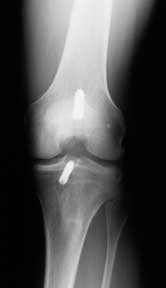

Improper placement of the ACL graft has been frequently cited as a cause of loss of knee motion. Grafts placed in what we call a “vertical orientation” as shown in the x-ray on the left can cause a limitation of knee motion. Unfortunately, if the limitation is severe and cannot be resolved with conservative rehabilitation measures, the graft has to be removed.

I place the ACL graft within the femoral and tibial footprint so that it occupies the central two-thirds or more of the footprint, to achieve an anatomic position (where the native ACL normally is found - see the x-ray on the right). To achieve this anatomic graft placement, sometimes a limited notchplasty is done to avoid a limitation of knee extension. I use the arthroscope to make sure that the graft position is exactly where I want it, and that there is no impingement of the graft against the lateral femoral condyle or notch when the knee is taken through the full range of motion on the operating table.